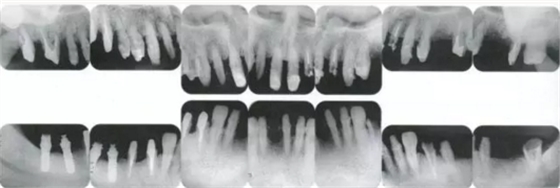

▲圖19-12

同時期的X光片。

▲圖19-14

佩戴最終修復體時的X光片。骨邊緣水平平坦,探診值維持在1~2mm。